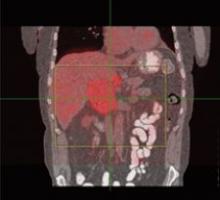

June 27, 2007 - Imaging Diagnostic Systems Inc. announced the release and publication of select results highlighting the advantages of using CT laser breast imaging as an adjunct to conventional mammography to improve detection of occult cancers in dense breasts.

"These CTLM results are being released as a response to the growing number of requests for performance statistics received from distributors and prospective customers worldwide. The results were obtained from our initial PMA-designed clinical study," commented Tim Hansen, IMDS Chief Executive Officer.